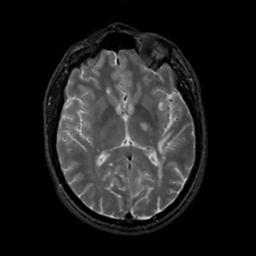

MR Study #2, February 17, 1991 -- Slice #26

[Home][Help][Clinical][Tour 1][Tour 2] Slice 26